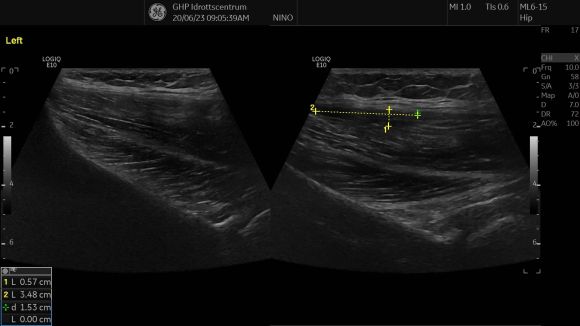

We did an ultrasound and detected a partial tear in the upper proximal part of the fascia to the gluteus medius. You can see the different echogenicity between the right and left pictures.  The hypoechoic area and the thickness of the fascia show the partial tear.

Don’t forget that partial tear can also be found in the upper proximal gluteal are to the ilium and not always in the trochanter area.